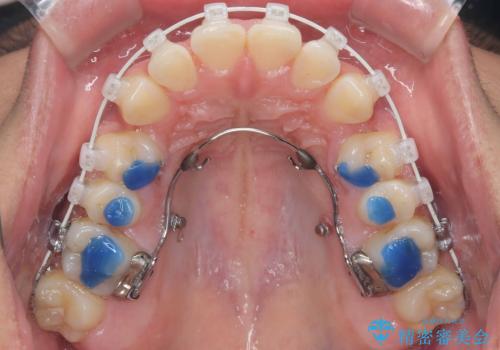

叢生(歯のデコボコ)の量が多く、加えてディープバイト(過蓋咬合)や重度の捻転も認められたため、リンガルアーチやマイクロインプラントなどの補助装置を併用し、治療を進めました。

治療途中では咬み合わせの改善を目的としてバイトアップを行い、歯の捻転や叢生を改善しつつ、機能的に安定した咬合を獲得しています。